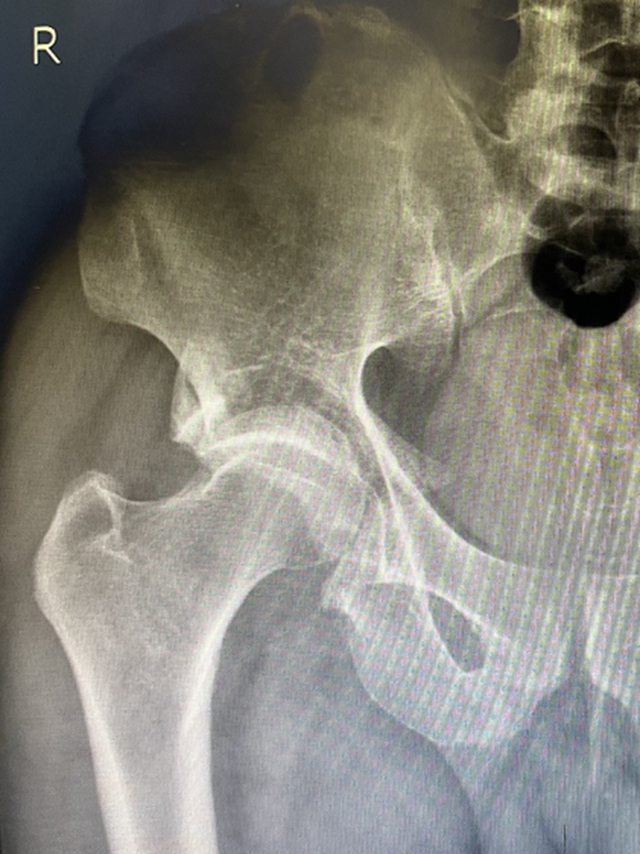

黄陈翼点开每张图片放大仔细查看,右侧髋臼骨折、双侧多发肋骨骨折、右侧桡骨远端撕脱性骨折、右侧尺骨茎突骨折、右腕三角骨骨折……

入院后,黄医生经过仔细查体,发现杨大爷生命体征平稳,全身多处骨折中,只有右侧髋臼粉碎骨折需要手术治疗。

据骨伤科创伤·正骨组主任刘宗超教授介绍:该患者为髋臼粉碎性骨折,为骨伤科常见骨折,该骨折如果处理不当会造成严重的关节功能障碍。近几年,科室接收治疗该类患者约500例以上,已掌握非常丰富的治疗经验。